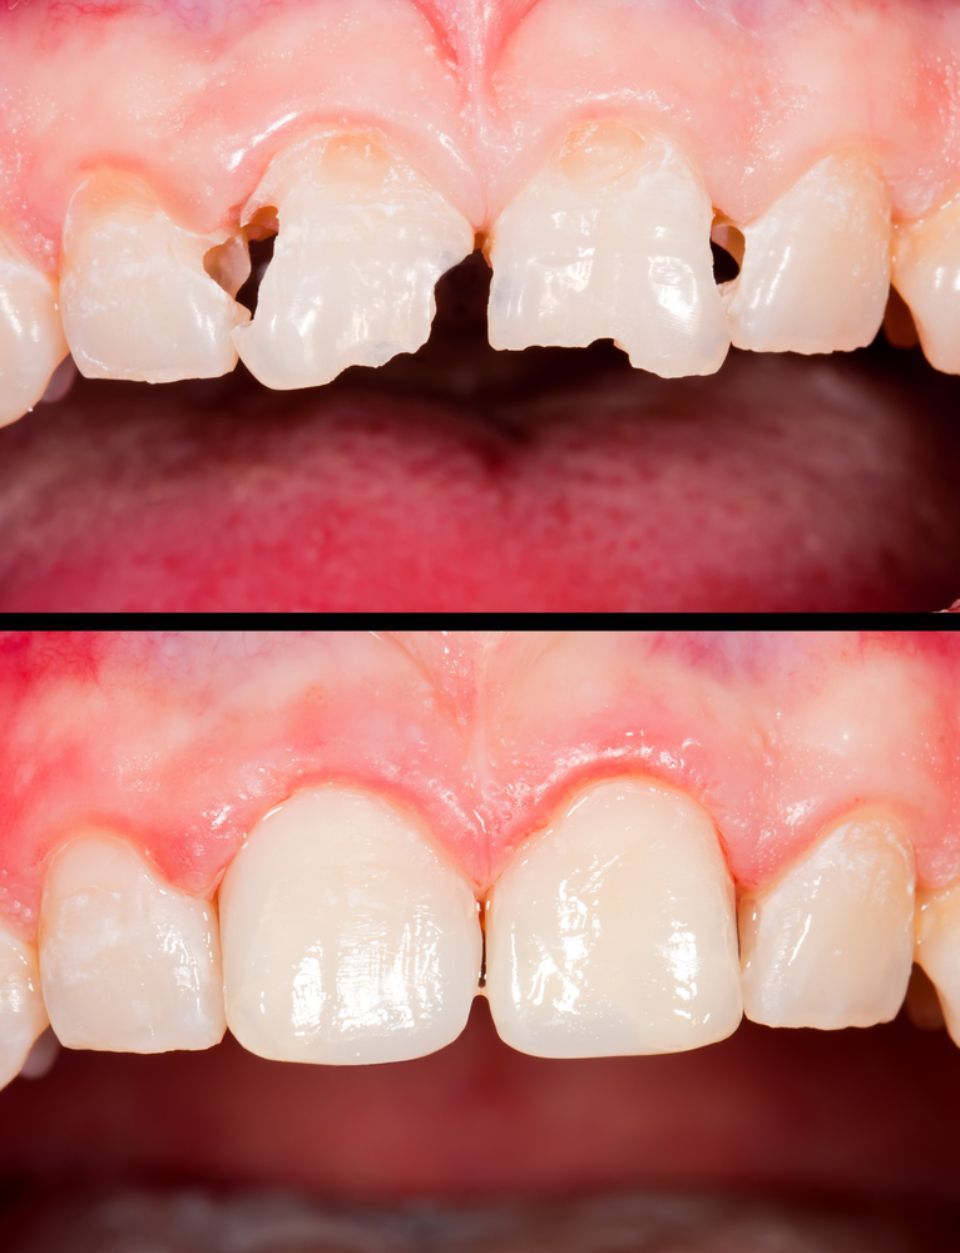

Odontologia restauradora/conservadora

Tal com el seu nom indica, tracta de conservar mitjançant la reconstrucció de les dents que s'han cariat o s'han fracturat, que han patit un traumatisme o estan erosionades; per preservar la seva funció com a dent.

Estètica dental

L'aparença de les dents es pot millorar. L'equip especialista avaluarà cada cas per adoptar la tècnica més adequada: blanquejament dental, restauracions amb composite, facetes de ceràmica, corones de metall-ceràmica, corones de zirconi, ortodòncia, cirurgia estètica periodontal.